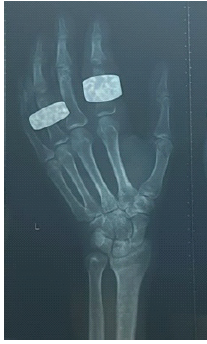

Distal Femur Extension Osteotomy for Fixed Flexion Deformity Following Distal Femur Malunion – A Case Report